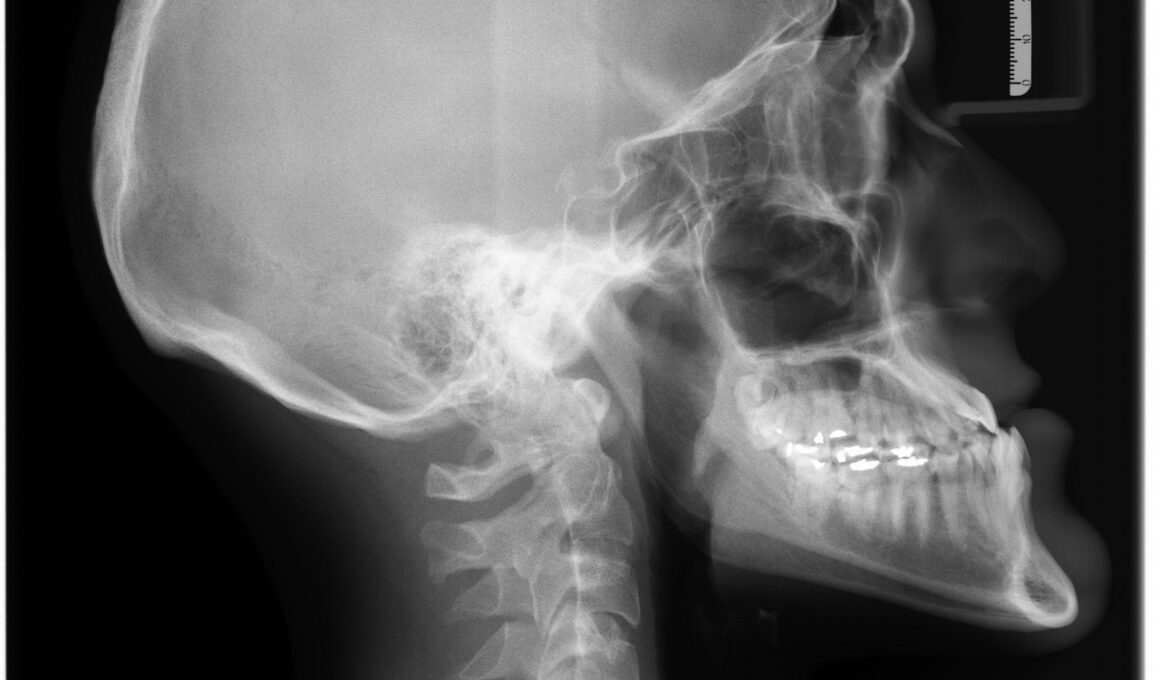

Fractures in bones can lead to severe complications and require urgent medical attention. Accurate diagnosis is crucial for prompt treatment. Common imaging techniques include X-rays, CT scans, and MRIs, which provide essential information regarding the location and severity of fractures. X-rays are often the first-line imaging choice for identifying fractures due to their accessibility and speed. They can quickly show where a break has occurred and how serious it is. In certain cases, conventional X-rays might not provide enough detail, necessitating further imaging. CT scans offer enhanced detail, particularly for complex fractures located in joints. MRI is valuable for soft tissue injuries accompanying bone fractures, providing a clearer picture of the surrounding tissues. Additionally, the use of advanced imaging technologies, like ultrasounds, is gaining popularity due to their non-invasive nature. Correctly interpreting these images demands a skilled radiologist. They collaborate with orthopedic specialists for optimal fracture management. Each imaging type has specific indications, allowing tailored treatment strategies according to fracture characteristics. Thus, timely diagnosis through appropriate imaging is essential for successful fracture management.

Among the various imaging techniques available, each serves a unique role in the diagnosis of bone fractures. X-rays are underlined as the cornerstone imaging tool due to their ability to quickly visualize fractures without the need for extensive preparation. Although they are effective, limitations exist, particularly in complex fractures. Computed tomography (CT) scans bridge this gap, offering three-dimensional images that provide greater clarity for difficult cases and those involving joint spaces. They are particularly beneficial when assessing spinal fractures or complex joints. Magnetic resonance imaging (MRI) is another valuable tool used primarily when soft tissue injuries are suspected alongside fractures. This imaging type does not use ionizing radiation, making it preferable for multiple studies or in scenarios involving children. MRI excels in detailing the surrounding anatomical structures, ensuring comprehensive evaluation. Ultrasound, while less common, is gaining recognition for monitoring and diagnosing fractures, particularly in children due to its safety profile. Each imaging modality has specific advantages and limitations, emphasizing the importance of selecting the right imaging technique based on individual patient circumstances.